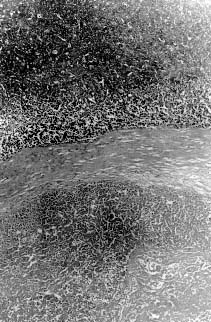

| Fig. 1. Large areas of necrosis scattered throughout the tumor forming lobules surrounded by well-defined fibrous strands. 62.5 x, H&E. | Fig. 2. Mitotic figures observed at high power field. 500 x H&E. |

Microscopically, the mass was composed of closely packed ribbons and nests of large round to polygonal cells with low amounts of basophilic cytoplasm and large round nuclei with prominent nucleoli divided into demarcated lobules by delicate septa of fibrous tissue. Large areas of necrosis werescattered throughout the mass forming lobules surrounded by well-defined fibrous strands (Fig. 2). The morphology of the tumor cells was consistent with a seminoma. In addition, clusters of small round to oval eosinophilic cells with condensed round nuclei were observed occasionally in the middle of some lobules. A minimum amount of hemorrhage was also observed.